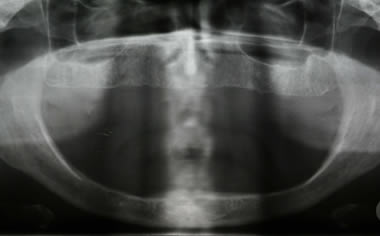

Full arches of teeth replaced by dental implants

Case One (5 images)

Full set of lower teeth fixed onto five dental implants.